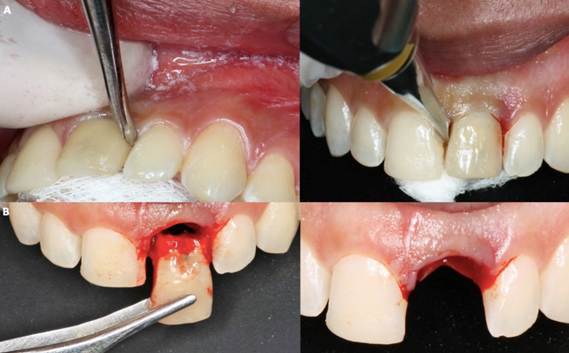

A 24-year-old male patient who required extraction of the upper left central incisor due to a corono-radicular fracture, reason for which is requested, panoramic radiography and cone beam, in which, as in the immediately previous case, the extraction was planned using a two-armed lever as an atraumatic alveolar preservation technique. During the clinical examination, it was observed at the level of the upper left central incisor, resin filling of 4 surfaces and slight redness was evident at the gingival margin (Figure 3.A and Figure 3.B). The extraction procedure was initiated by applying the strength of the two-arm lever, the straight elevator is in a horizontal position resting on the mesial and distal surfaces have the greatest possible palatal rest and resistance in the mesial and/or disto-vestibular areas; that generates an extrusive dental dislocation that combined with the vestibular palatine grip with the left hand helps to avoid compromising the vestibular table, then it is produced in the first instance, tooth crown extraction (Figure 4.A and Figure 4.B), by the corono-radicular fracture already mentioned, then its proceed to the dental root´s extraction, using lever of the second degree, without compromising the vestibular and palatal tables. Once confirmed the integrity of the vestibular wall and the gingival biotype: type I socket, 1cc of Puros® particulate cortical bone (250-1000 microns) is used for the graft. Subsequently, Zimmer TSV 3.7 * 13mm implant was placed (Figure 5). The implant was prepared and placed 2.5mm from the gingival margin to achieve primary fixation, a surgical cover screw was placed, the cavity was occluded with a collagen membrane (CollaTape®) and sutured transverse and horizontally with acid polyglycolic 5-0, followed by a provisional restoraion, finally, the patient is prescribed oral capsules of dicloxacillin 500mg and nimesulide tablets orally 100mg. After five months of clinical and radiographic controls, the second phase begins. The patient received a metallic ceramic crown with functional and aesthetic results after 18 months of continuous controls.